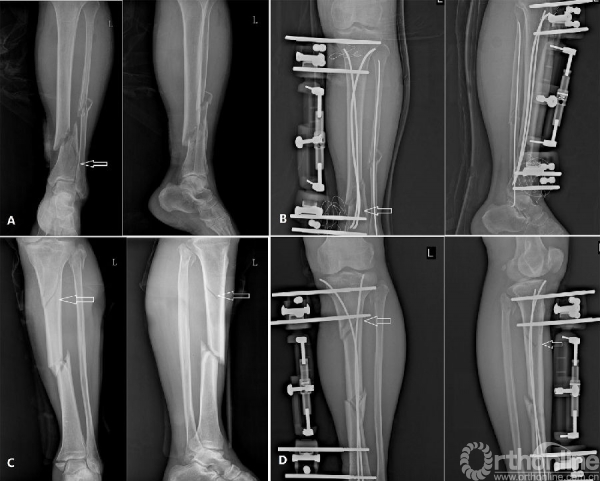

本组手术时间为25~60min,平均35min;术中平均透视19 次,术中均无输血,出血20~50ml。24 例获5耀18个月随访,平均12 个月。4 例患者钉道皮肤发红,未经特殊处理自愈。2例患者发热超过39益,经对症处理好转。16 例开放性骨折患者均行一期清创内固定术,其中2 例行创面负压吸引术(VSD),术后创口愈合良好。最早术后4 周X 线片显示骨痂出现,平均4~12周。外固定支架动力化时间8~12周,平均10 周;外固定支架去除时间12~16 周,平均13 周;TENs取出时间6~18 个月,平均9 个月。8 周开始练习走路,完全负重时间为10~18周,平均14周。临床及影像学骨折愈合时间为6~15个月,平均7.5 个月。本组无感染、脂肪栓塞、骨不连以及再骨折发生。按Johner-Wruhs方法评价功能,本组优18 例,良4 例,中2 例,差0 例,以优良率作为满意标准,总体满意率为91.7%。典型病例图片见图1-2。

图1 右胫腓骨粉碎性骨折(男性患者,31 岁;车祸伤致右胫腓骨粉碎性骨折、外侧平台塌陷、右下肢软组织严重挫伤;A、B:右下肢肿胀明显、皮下瘀血;C、D:CT 平扫,白箭头示胫骨外侧平台塌陷骨块;E、F:X线平片,黑箭头示胫骨干粉碎性骨折)

图2 右胫腓骨粉碎性骨折术后[A、B:患者髓内髓外系统联合固定术后1 周X 线,白色箭头示胫骨平台塌陷位置借助TENs复位后;黑色箭头示胫骨干粉碎性骨折复位术后;C、D:术后4 周,胫骨平台关节面基本恢复(白箭头所示),胫骨干少量骨痂出现(黑箭头所示);E、F:术后8 周,平台骨折线模糊,胫骨干大量骨痂出现;G、H:术后半年,外固定拆除后,平台关节面恢复良好,胫骨干骨折达骨性愈合。